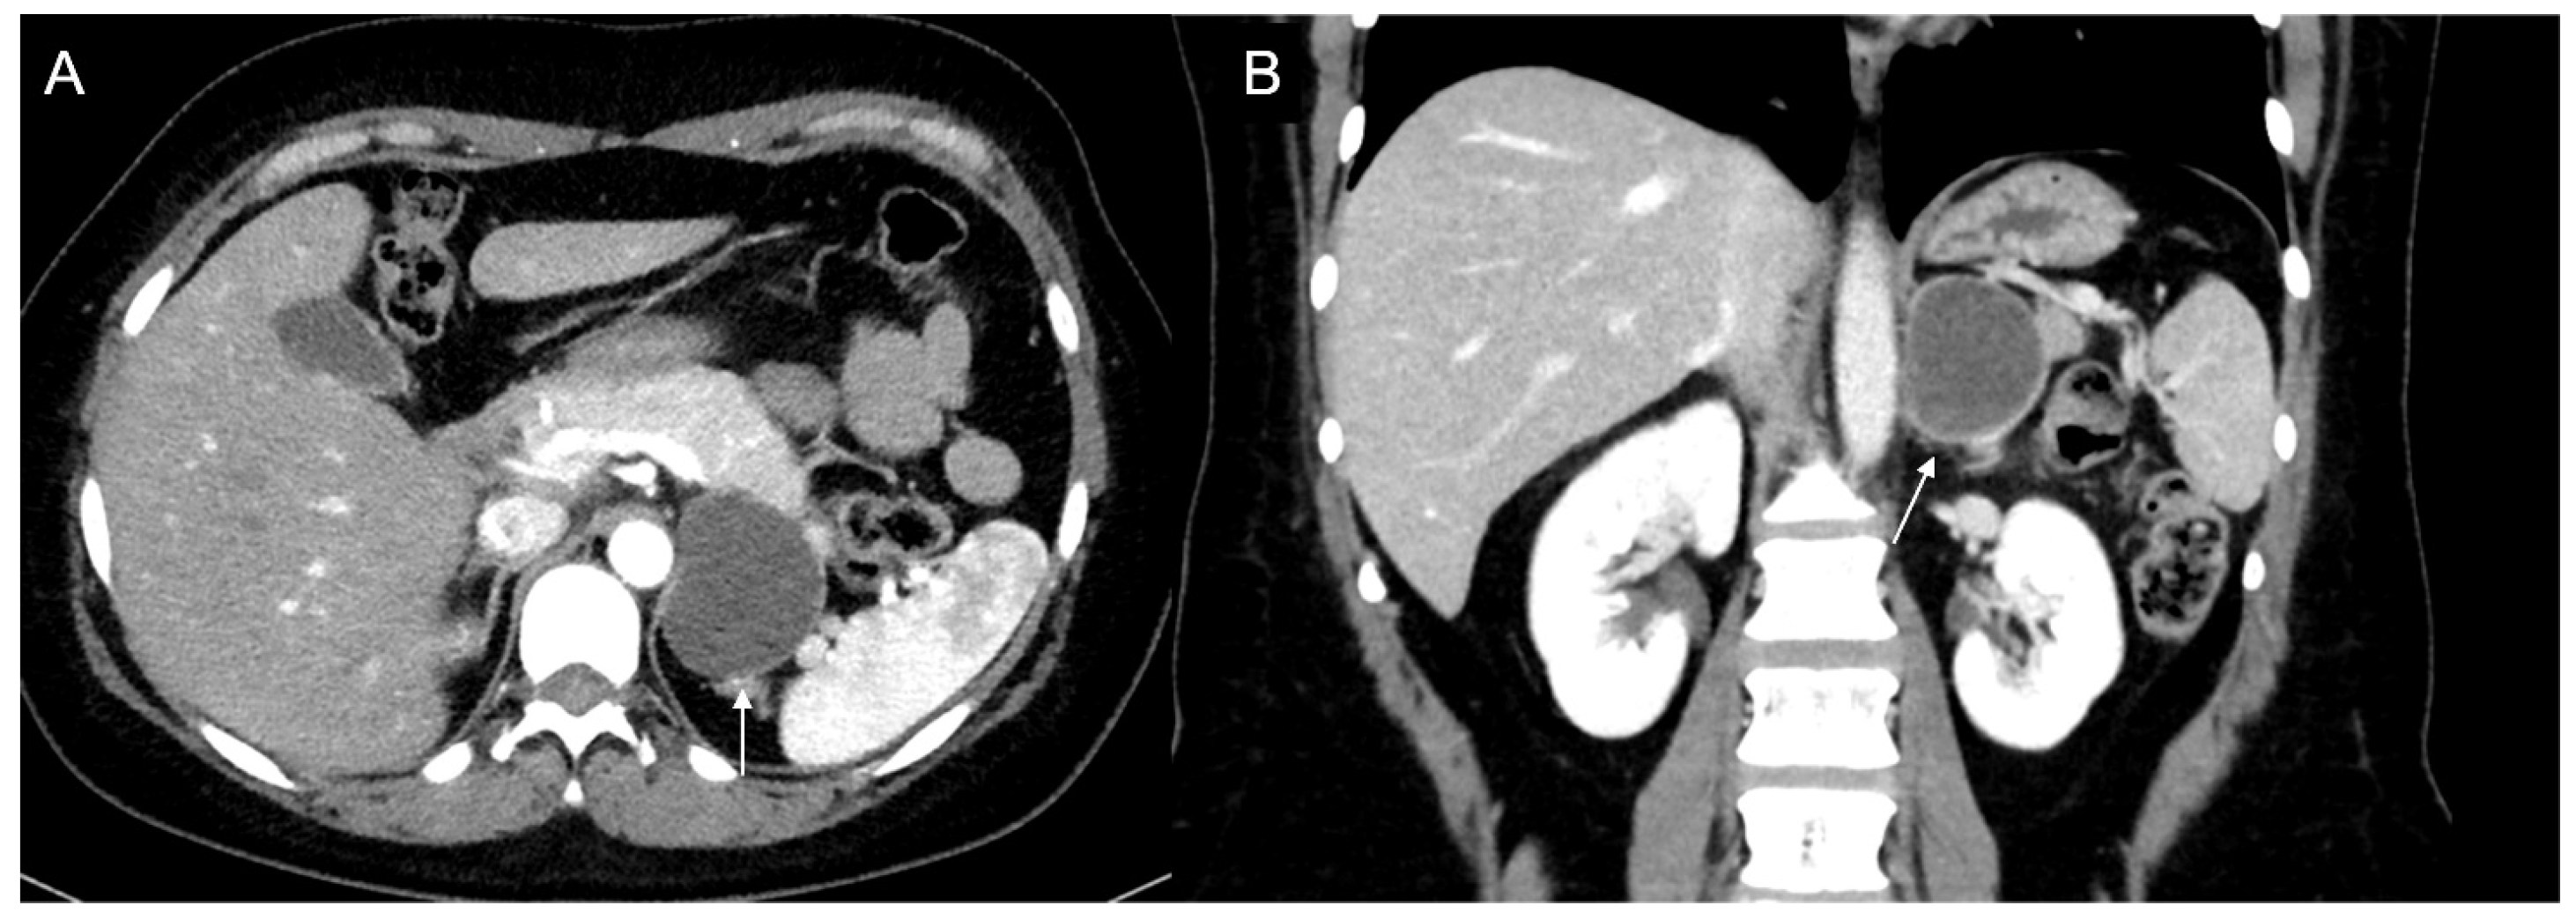

Figure 14.

Axial unenhanced (a), arterial (b), and coronal venous (c) CT phases show a lung carcinoid metastasis (arrow) of the left adrenal gland. Additional hypervascular metastasis can be seen in the liver, particularly in the arterial phase.

More specifically, the study by Andersen et al. focused on adrenal metastases from lung cancer [101]. They found several texture parameters statistically significantly in differentiating metastatic and benign adrenal lesions in patients with lung cancer (Figure 15).

Figure 15.

Segmentation of the metastatic lesion (arrow) of the left adrenal gland (same patient of Figure 4) on venous phase CT, using 3D-Slicer Software, version 4.11.